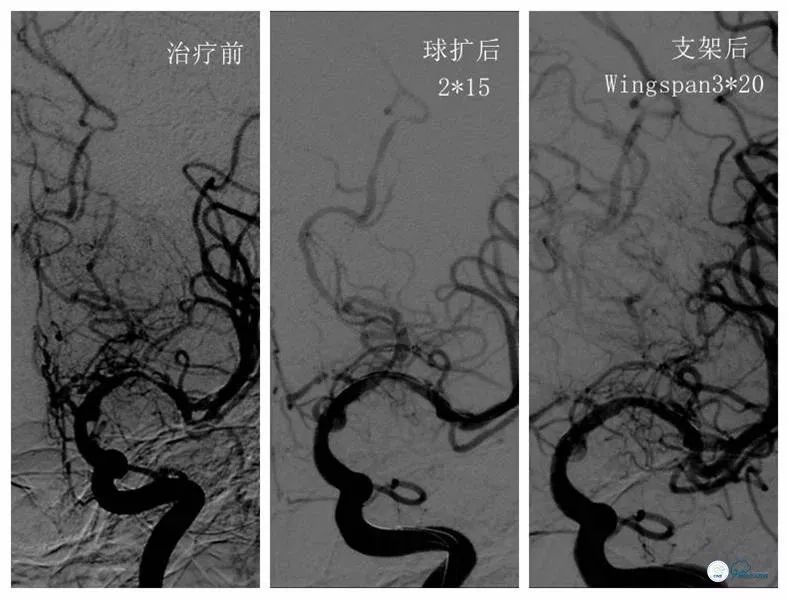

2017-11-20行左侧大脑中动脉M1段支架植入术(Gateway 2.0×15mm,Wingspan 3.0×20mm)(图2)。

图2